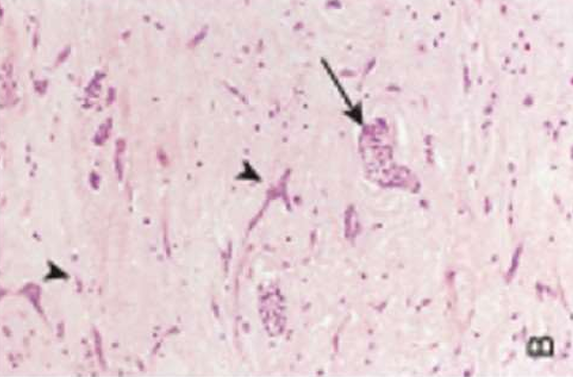

Hypertrophic Cardiomyopathy

Myocyte disarray, extreme hypertrophy, and characteristic branching, & interstitial fibrosis.